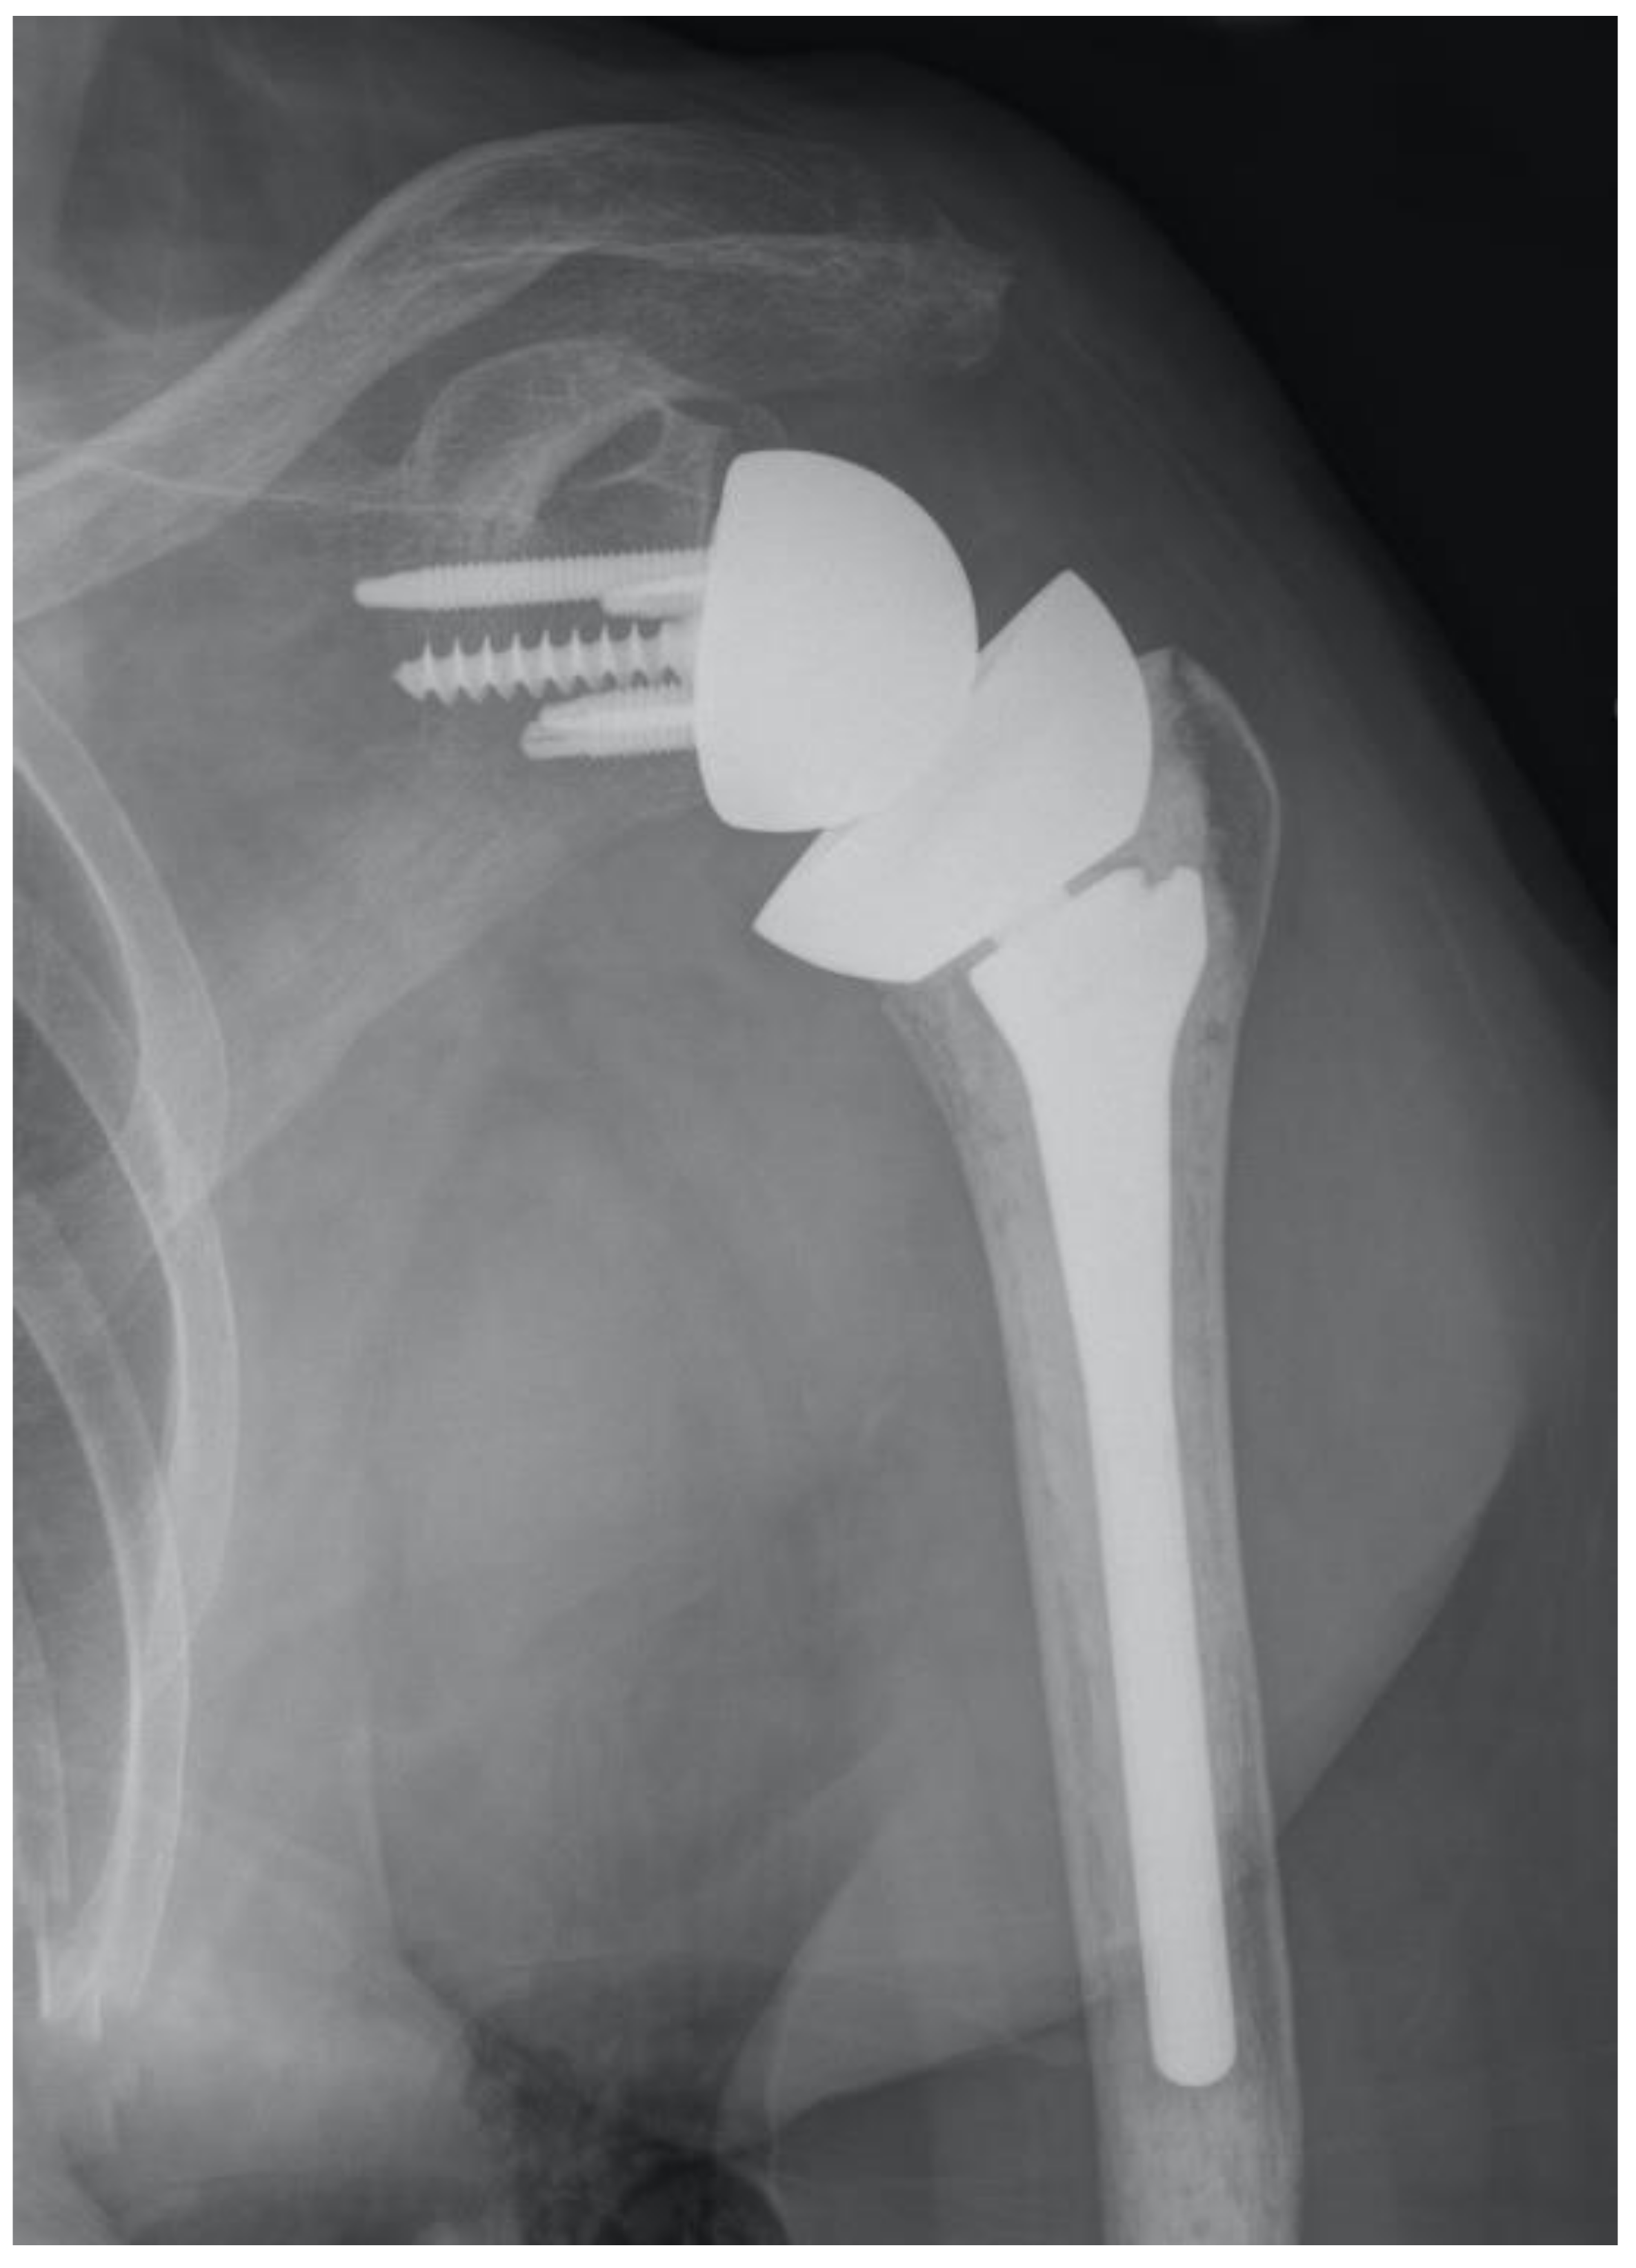

However, the onlay vs. inlay controversy should probably be abandoned for two reasons. Firstly, there is a high level of variability regarding how much lateralization and distalization are provided by the many implants in the market [25]. Classifying them as onlays or inlays is an oversimplification. What matters is where the humerus “lands” for a specific glenoid reconstruction, depending on the humeral implant selected and where it is implanted. This will affect the length and the moment arm of the deltoid and rotator cuffs [26]. Secondly, surgeons may implant inlay components in an onlay fashion or the other way around. For example, the original prosthesis designed by Dr. Frankle was an inlay design; however, its proximal portion was relatively large and could not be fully inset in the humeral metaphysis of many patients, thus resulting in an onlay application of an inlay design (Figure 5). By the same token, if thicker polyethylene bearings or a metal spacer are added to an inlay prosthesis to guarantee adequate stability, the pivot point is at an onlay level despite the implant being designed as an inlay. Consequently, even though implants that allow placement of the pivot point at or below the cut surface of the humerus are necessary to optimize soft tissue tension across the whole spectrum of shoulder replacements, in many shoulders, these inlay components will behave as onlay ones because thicker polyethylenes may be needed to avoid dislocation, especially in the cuff-deficient shoulder. The ideal degree of humeral lateralization probably varies from individual to individual depending on the underlying diagnosis and other characteristics.

Figure 5.

This implant was designed as an inlay, but its large size resulted in an onlay application most of the time.